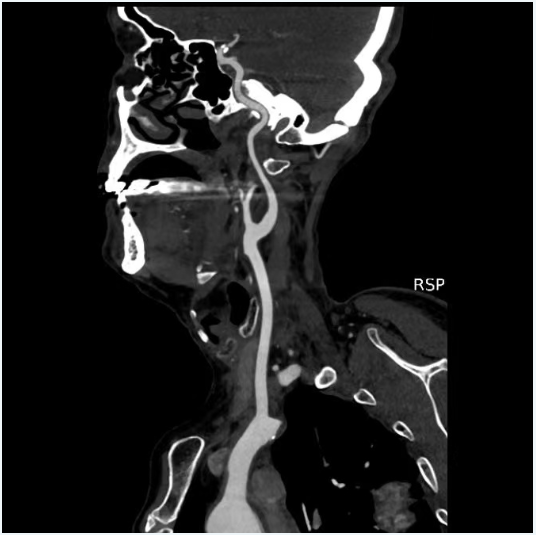

現(xiàn)病史:患者1月前因“左側偏癱,言語含糊”就診我科,溶栓后僅留有言語含糊(NIHSS評分1分)出院,出院診斷為“腦梗死,右側頸內(nèi)動脈C6段重度狹窄,高血壓病3級極高?!?,此次為進一步處理血管回診我科。

二、術前影像

擬行手術方案:右側頸內(nèi)動脈C6段狹窄球囊擴張+顱內(nèi)藥物洗脫支架植入。